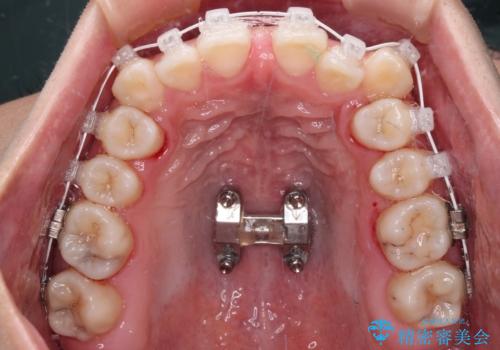

上顎歯列が狭窄していたため、急速拡大装置により上顎骨を側方に拡大し、その後ワイヤー装置にて矯正治療を行うこととしました。